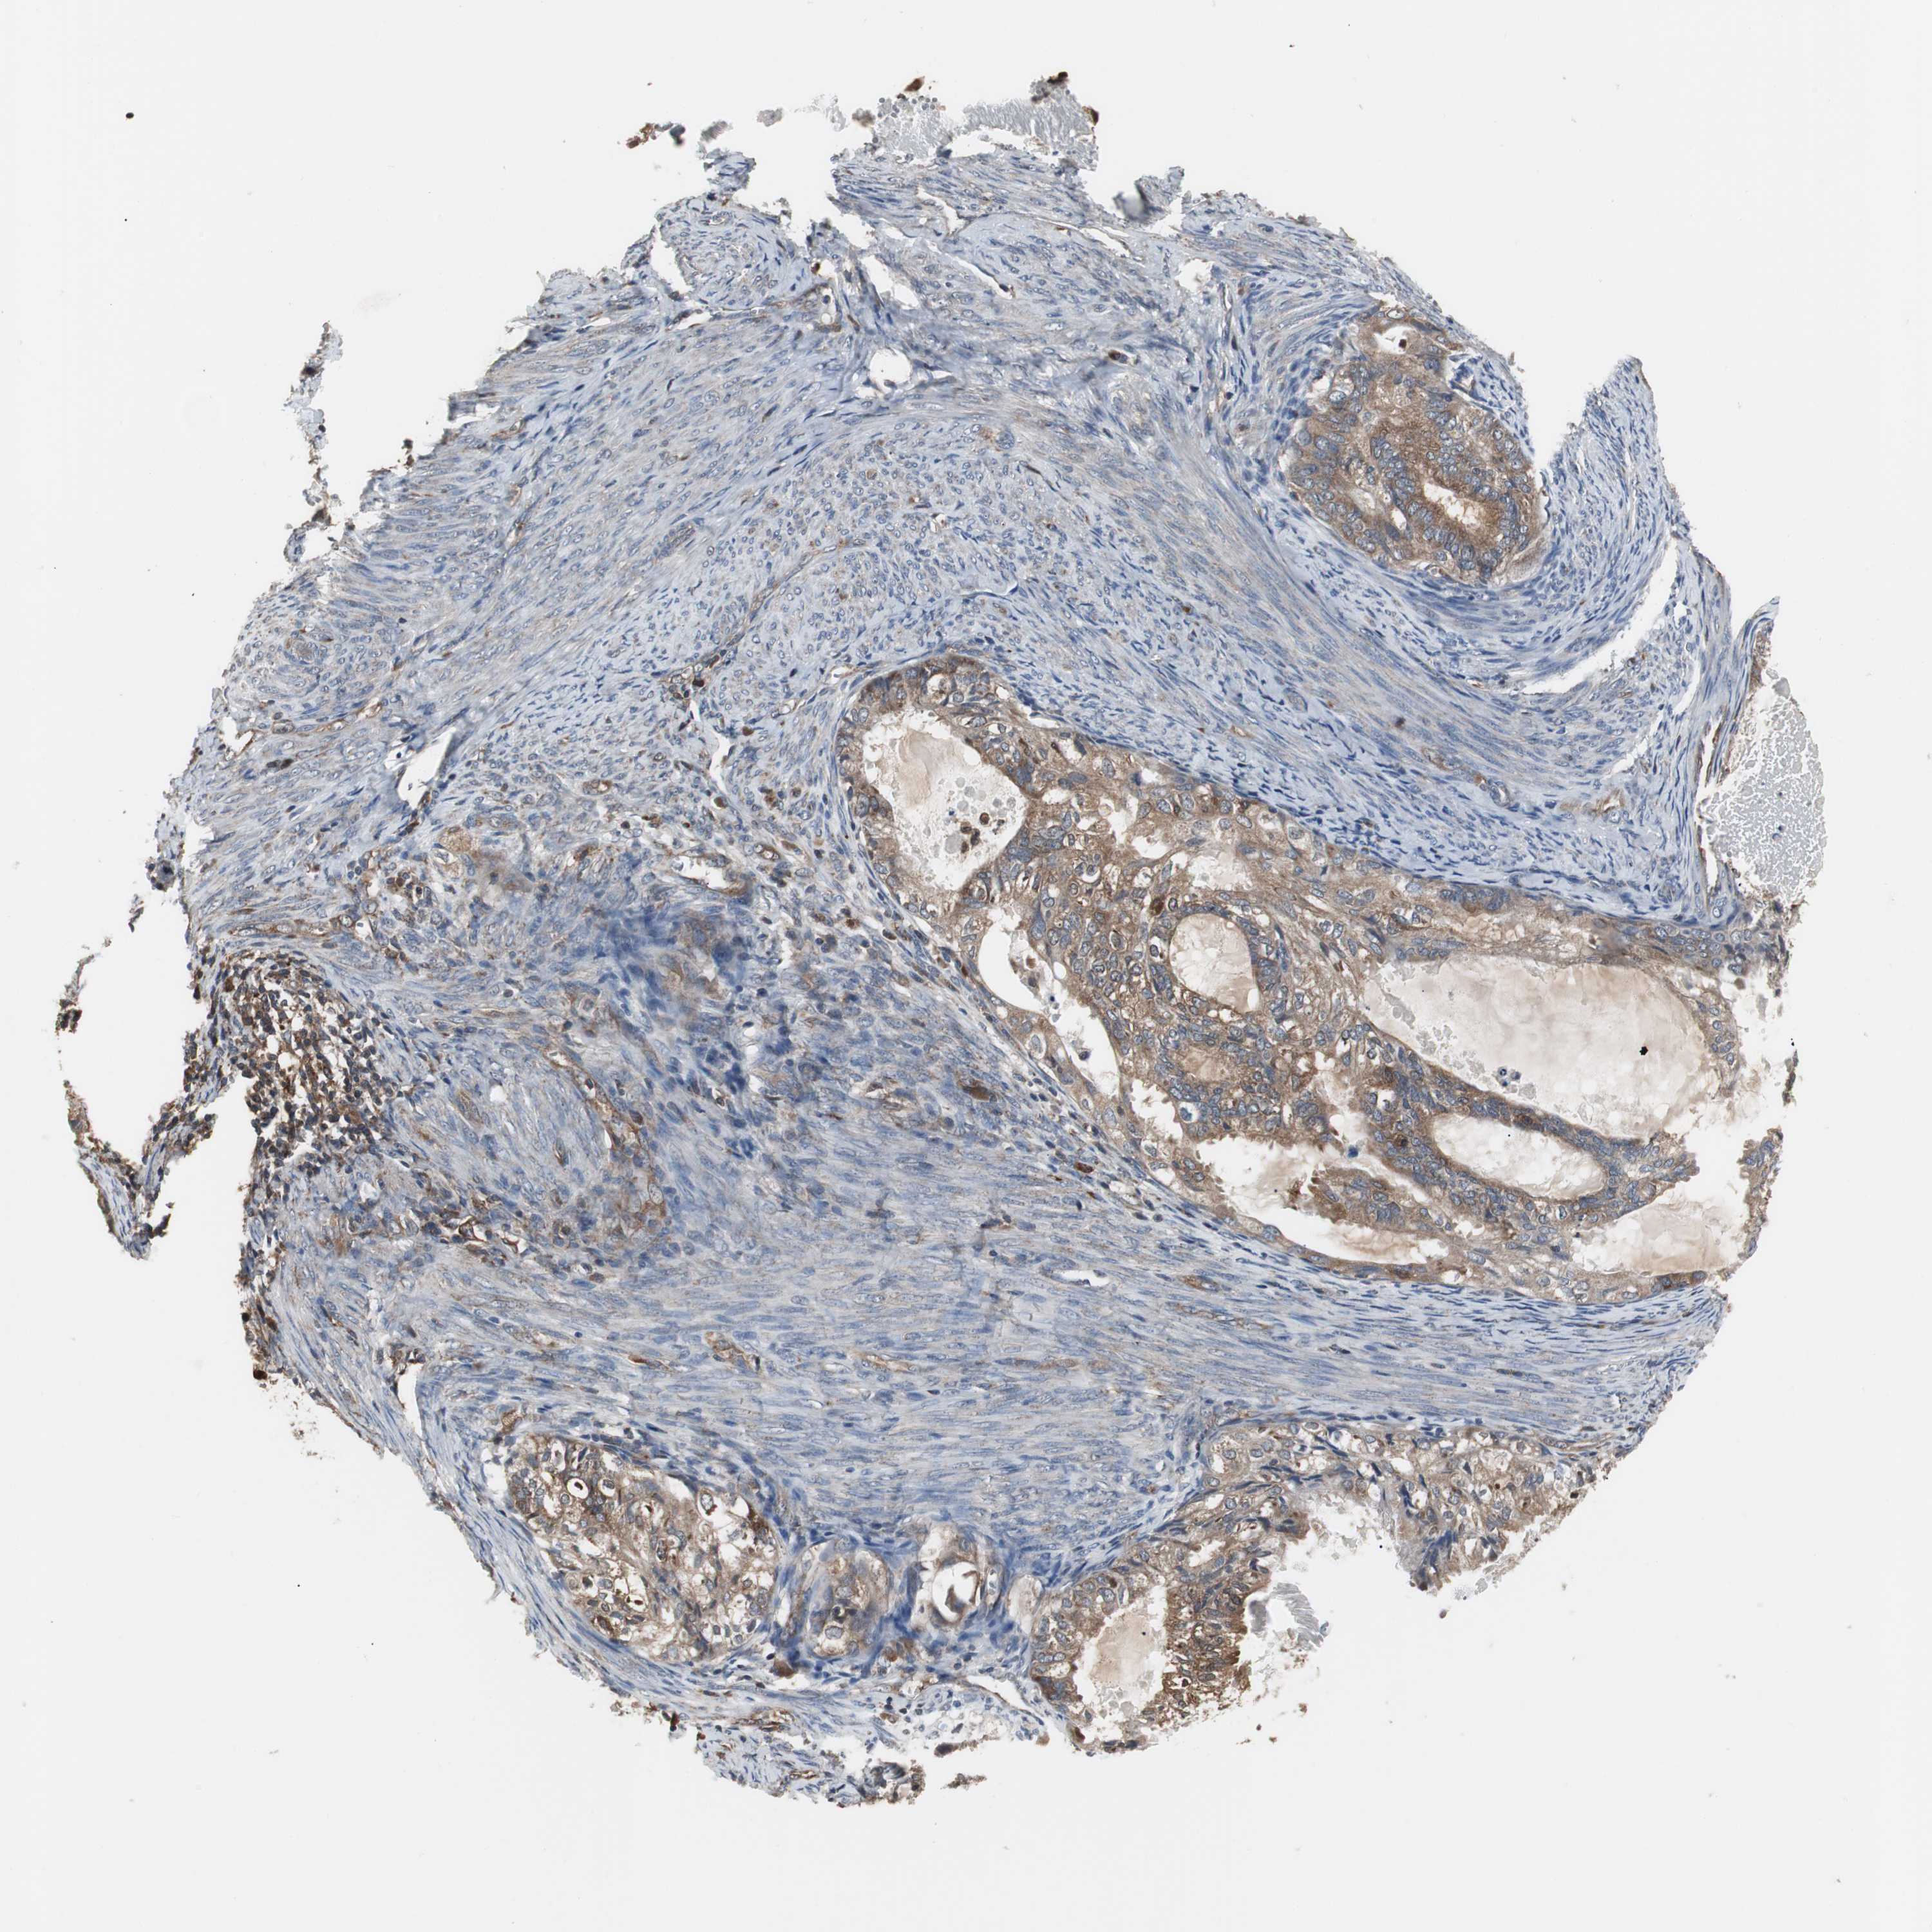

CERVICAL CANCER - Protein expressioni

A mouse-over function shows sample information and annotation data. Click on an image to view it in a full screen mode. Samples can be filtered based on level of antibody staining by selecting one or several of the following categories: high, medium, low and not detected. The assay and annotation is described here.

Note that samples used for immunohistochemistry by the Human Protein Atlas do not correspond to samples in the TCGA dataset.

Antibody stainingi

Antibody staining in the annotated cell types in the current human tissue is reported as not detected, low, medium, or high, based on conventional immunohistochemistry profiling in selected tissues. This score is based on the combination of the staining intensity and fraction of stained cells.

Each image is clickable and will lead to virtual microscopy that enables deeper exploration of all samples and also displays staining intensity scores, fraction scores and subcellular localization as well as patient and tissue information for each sample.

Antibody HPA006471

Staining

High

Medium

Low

Not detected

Intensity

Strong

Moderate

Weak

Negative

Quantity

>75%

75%-25%

<25%

None

Location

Nuclear

Cytoplasmic/membranous

Cytoplasmic/membranous,nuclear

Squamous cell carcinoma, NOS

Adenocarcinoma, NOS